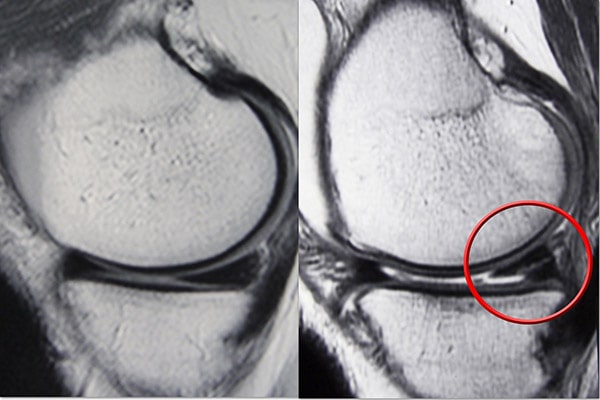

磁共振成像 (MRI) 掃描。 MRI 掃描可評估膝關節的軟組織,包括半月板、軟骨、肌腱和韌帶。

半月板可能因急性創傷或隨著時間的推移發生退行性變化而撕裂。眼淚通過它們的外觀以及半月板發生撕裂的位置來記錄。常見的撕裂包括桶柄、襟翼和徑向。